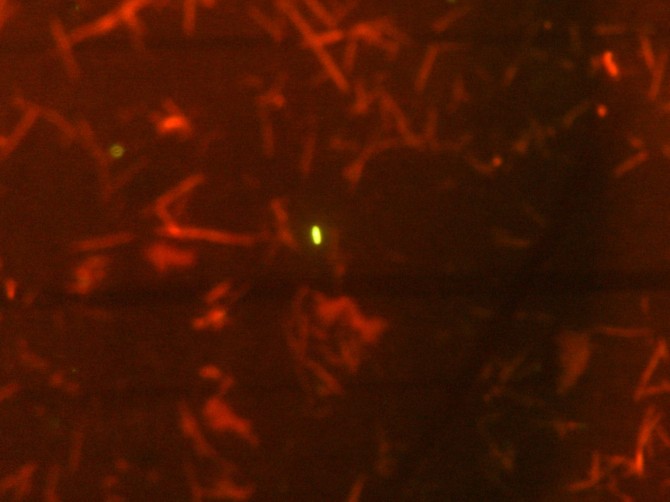

Imagen de microscopía de bacterias vivas (verde) en una muestra de bilis humana. (Foto: CSIC-IPLA)